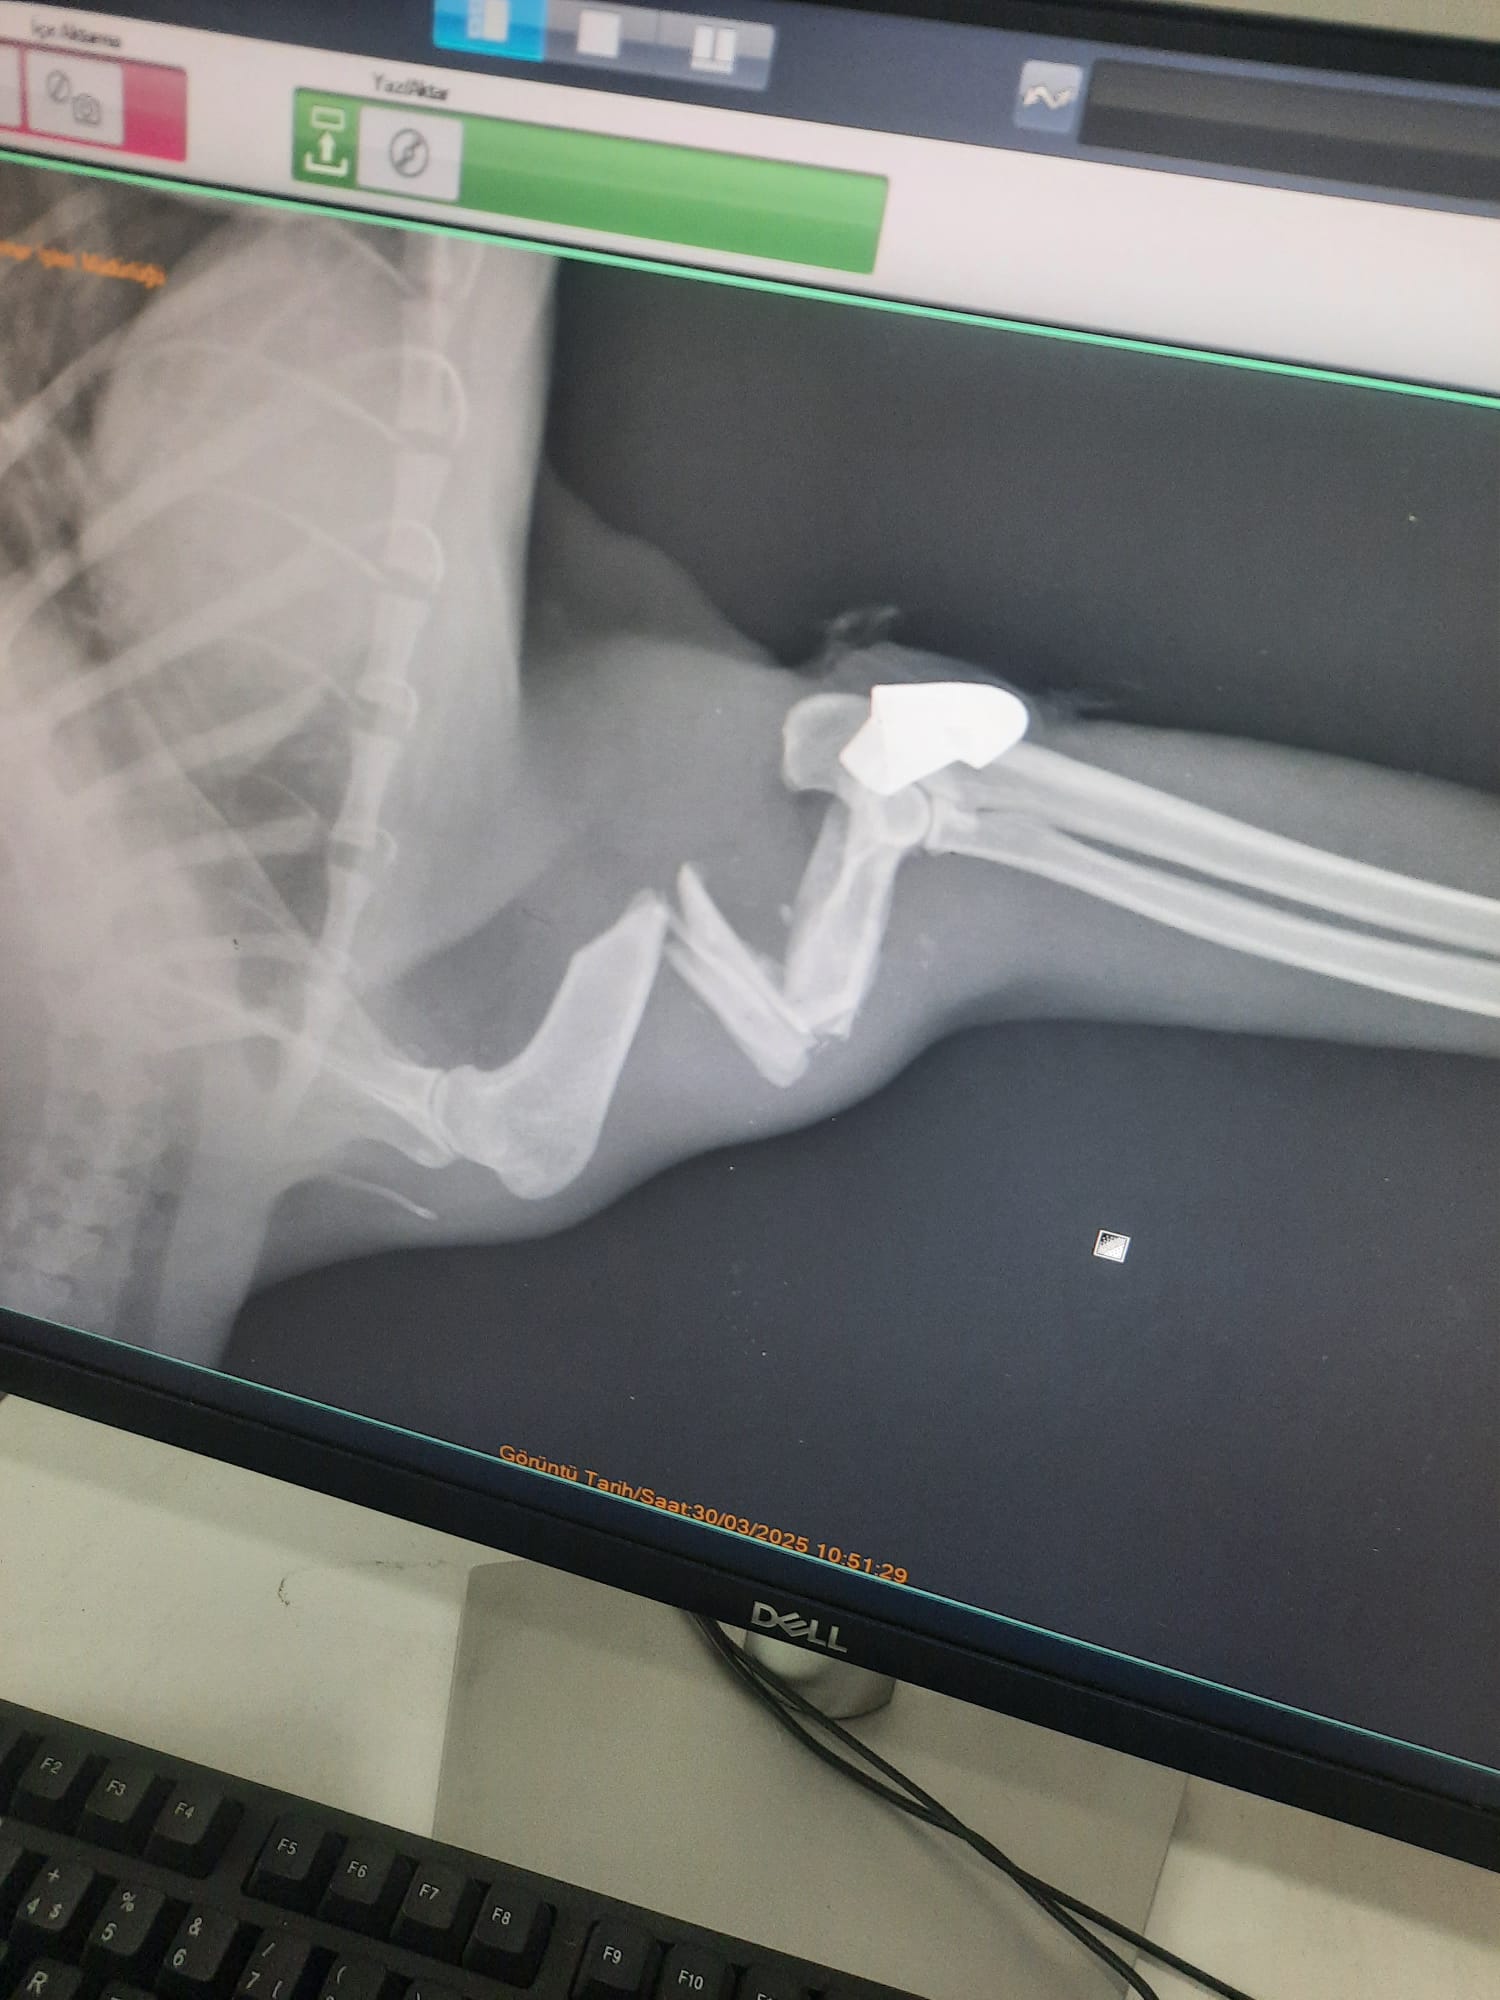

Kilimli ilçesinde, Seda Özkaya’nın baktığı sokak kedisi, yaklaşık 2 ay önce kayboldu. Önceki gün ortaya çıkan kedisinin patisinin üstüne basamadığını fark eden Özkaya, hayvanı tedavisi için Zonguldak Belediyesi Veteriner İşleri Müdürlüğü’ne götürdü. Burada tedaviye alınan kediye röntgen çekilince patisinde mermi olduğu görüldü. Mermi, yapılan ameliyatla çıkarıldı.

Zonguldak Belediyesi Veteriner İşleri Müdürü Rıza Akçay, “Röntgenlerini falan çektik. Sonuç olarak, ameliyatını yaptık. Ameliyat başarılı geçti. Eski sağlığına inşallah kavuşacak. Yorgun mermi isabet etmiş. Çekirdeği zaten üzerindeydi. Onun için diyoruz zaten yorgun mermi. Gerekeni yaptık” dedi.